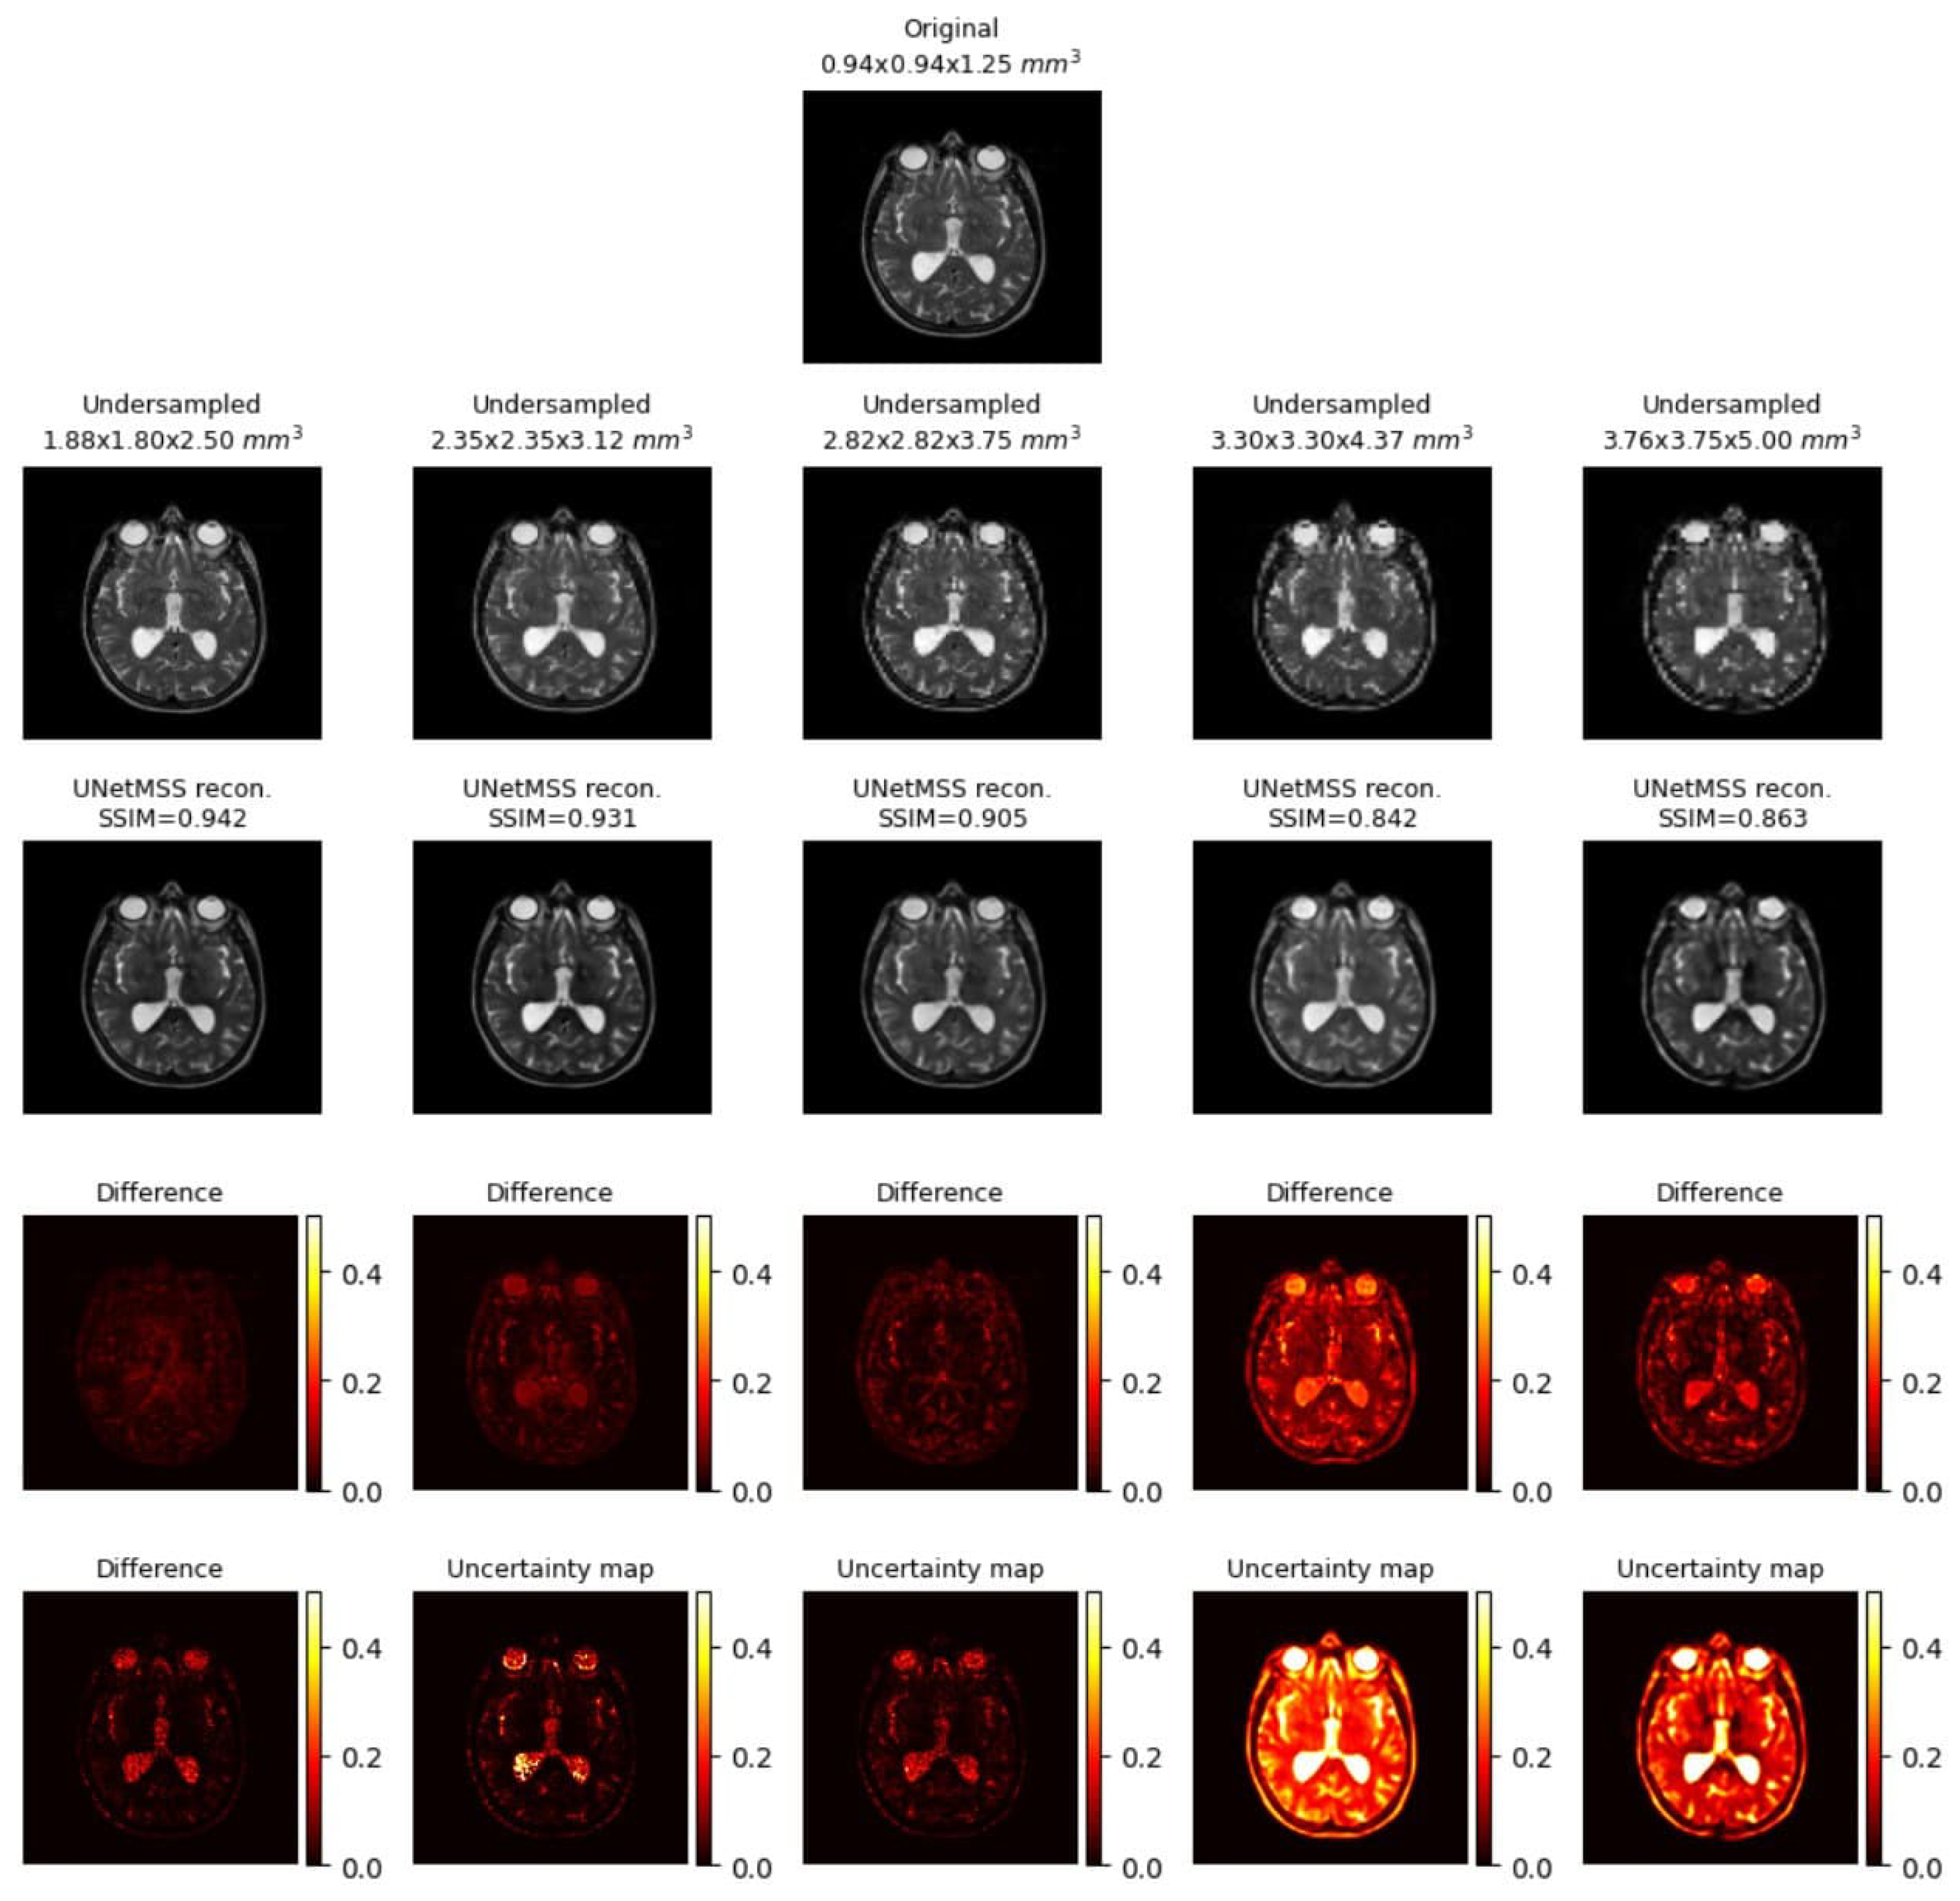

- Visualising individual model results for all the acceleration factors.

3.1.2. Main Experiments and Model Comparison

Uncertainty Mapping